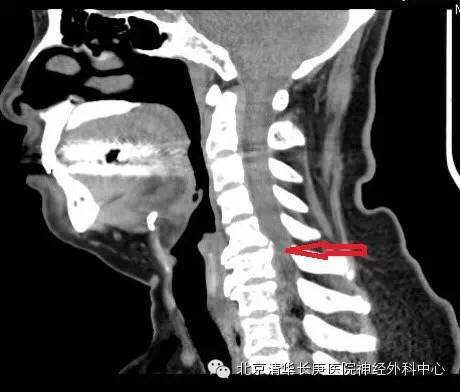

CT显示:C5-6,6-7椎间盘突出,后纵韧带骨化